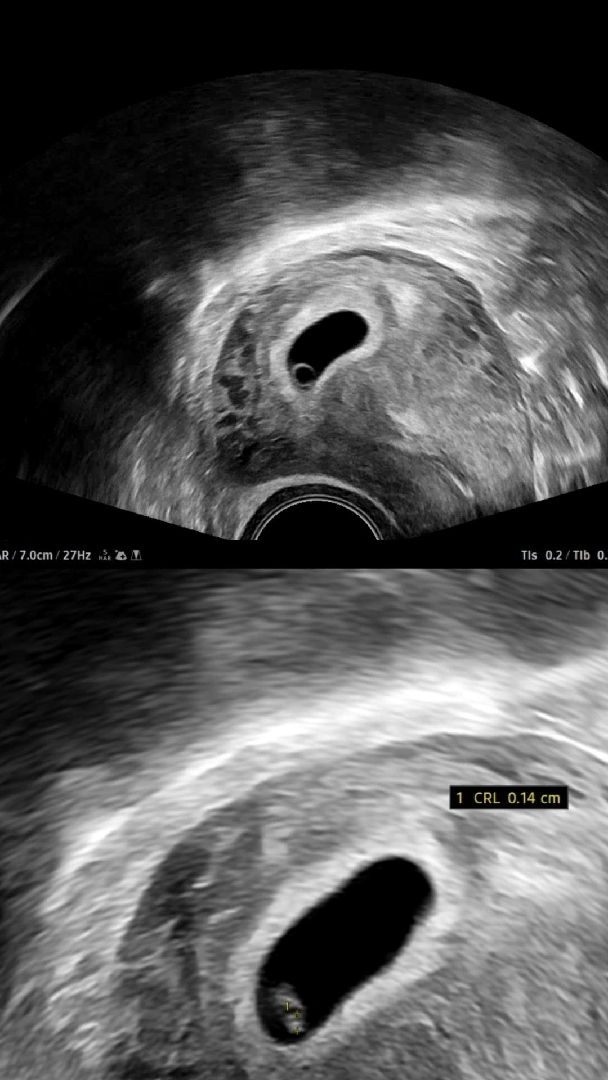

6주1일차 집들이 성공👼🏡💍

막생➡️7/11 5주차때는 집이 0.4cm였는데 오늘은 아기가 고만했어요🥹🥹 일주일 사이에 너무 잘 커줘서 고맙고 좋네요❤️ 심장은 반짝임만 봐서 5일뒤에 심장소리 들으러 갑니다!!